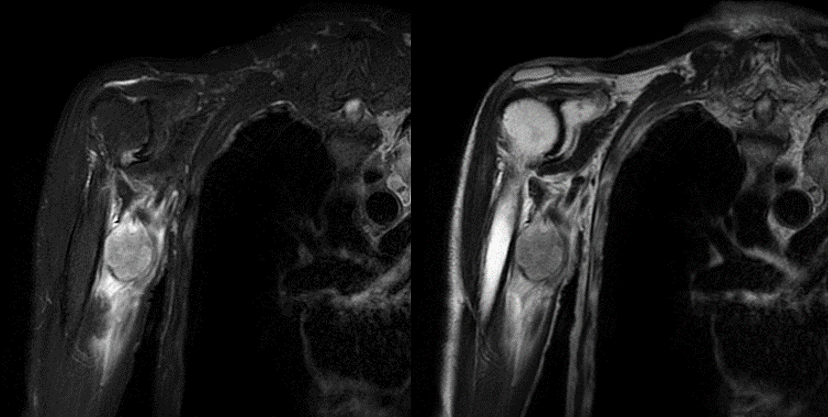

従来の3ポイントDIXONのIDEAL法の他に2ポイントDIXONのFlex法が使用可能となった。Flex法は、均一な脂肪抑制画像を取得でき、IDEALほど時間延長はなく非常に使い勝手の良いシーケンスである。手指や足趾などの磁場不均一が生じやすい部位に対しても、簡便に均一な脂肪抑制画像が取得でき大変重宝している。軟部腫瘍精査を目的とする際は、均一な脂肪抑制画像だけではなくIn phase画像が取得できるので、totalの検査時間が短縮され非常に有用である。